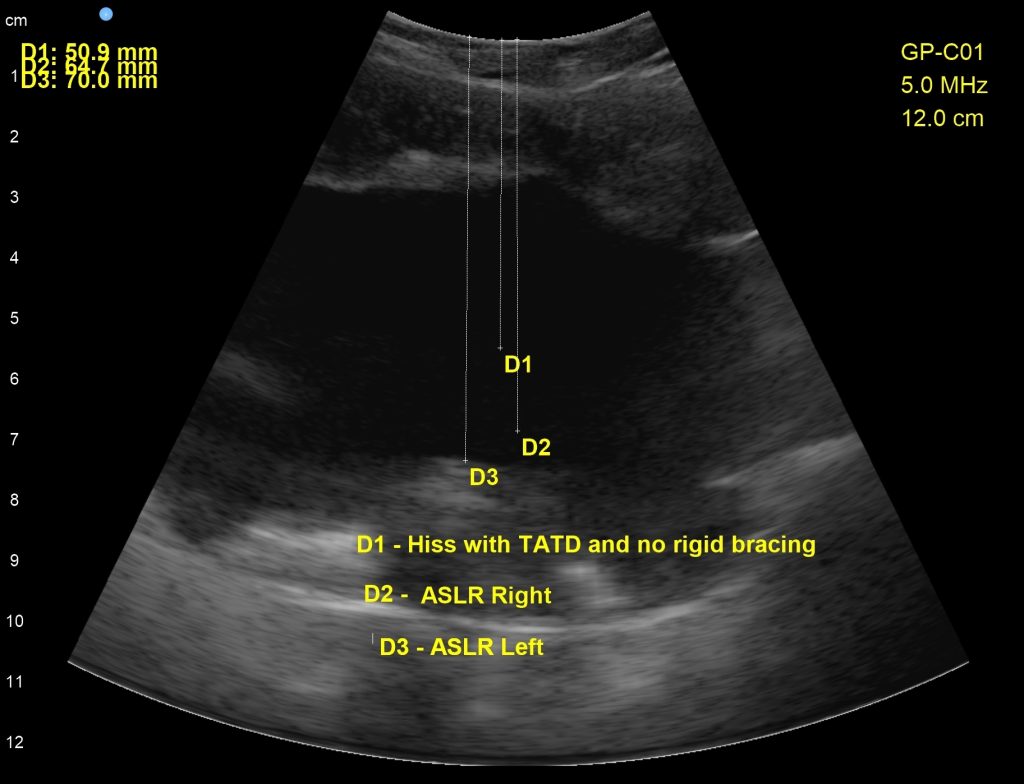

In the third scan, we experimented with the baseline of the new cue to hiss with a light Umbrella Breath, then tested active straight leg raising on the right and left. The downward descent of the pelvic floor was lessened using the new cue, however, we still have work to do, because lifting the left leg was substantially harder than lifting the right (as visualized by greater downward pressure on the pelvic floor than the right lift)